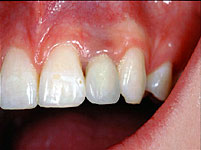

Einzelne Zähne können auch in völlig gesunden Gebissen durch Unfall oder Entzündungen verloren gehen, ebenso sind besonders die oberen seitlichen Schneidezähne häufiger nicht angelegt. Die drei Bilder zeigen den Ersatz eines nicht angelegten seitlichen oberen Schneidezahnes bei einem Jugendlichen.